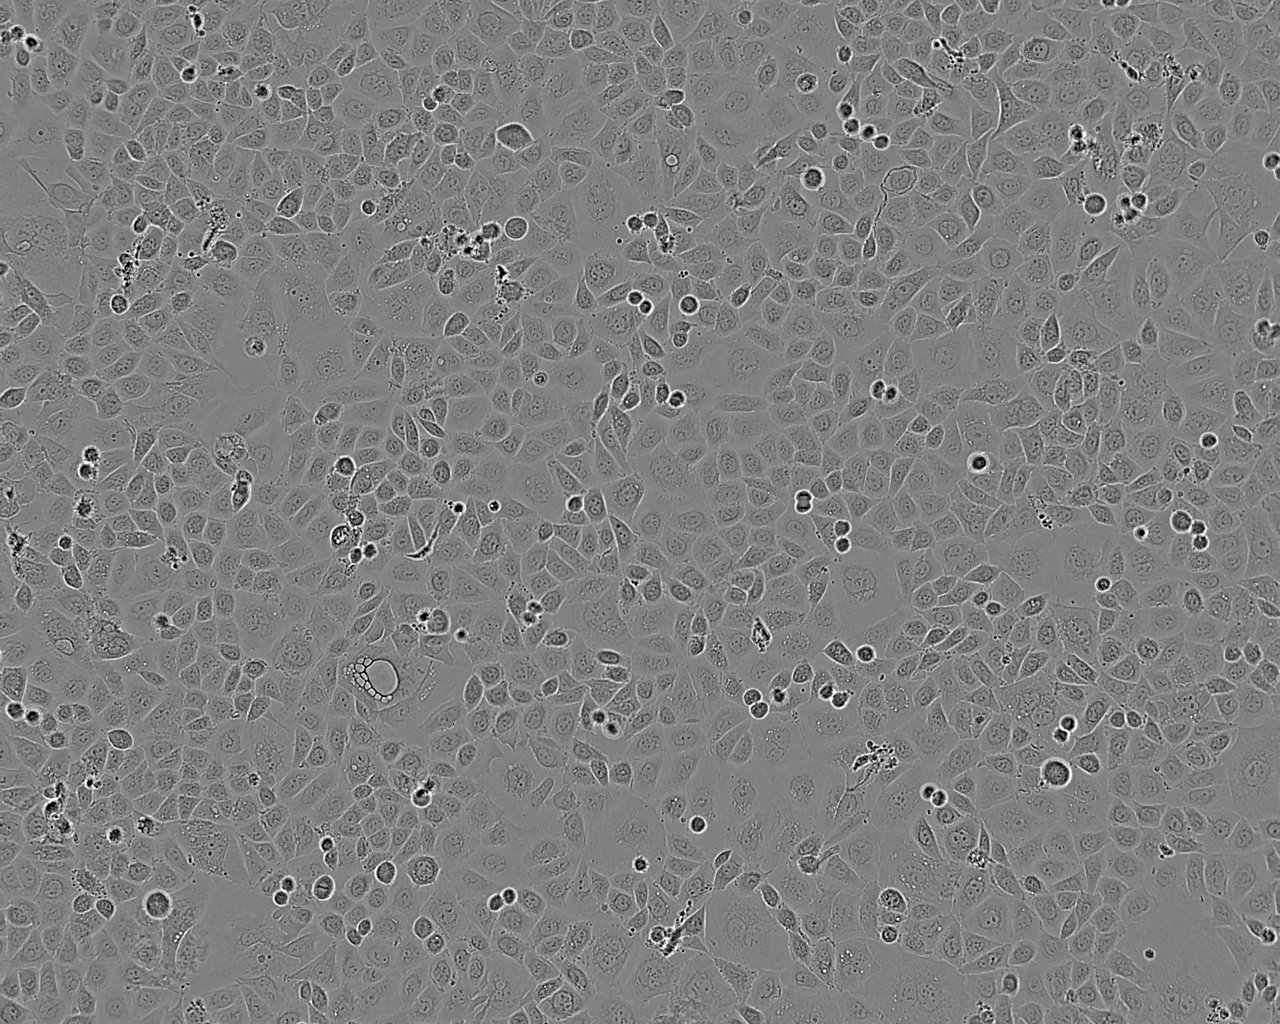

SKO-007 epithelioid cells

细胞形态:上皮细胞样

细胞生长:贴壁

细胞生长特性:悬浮